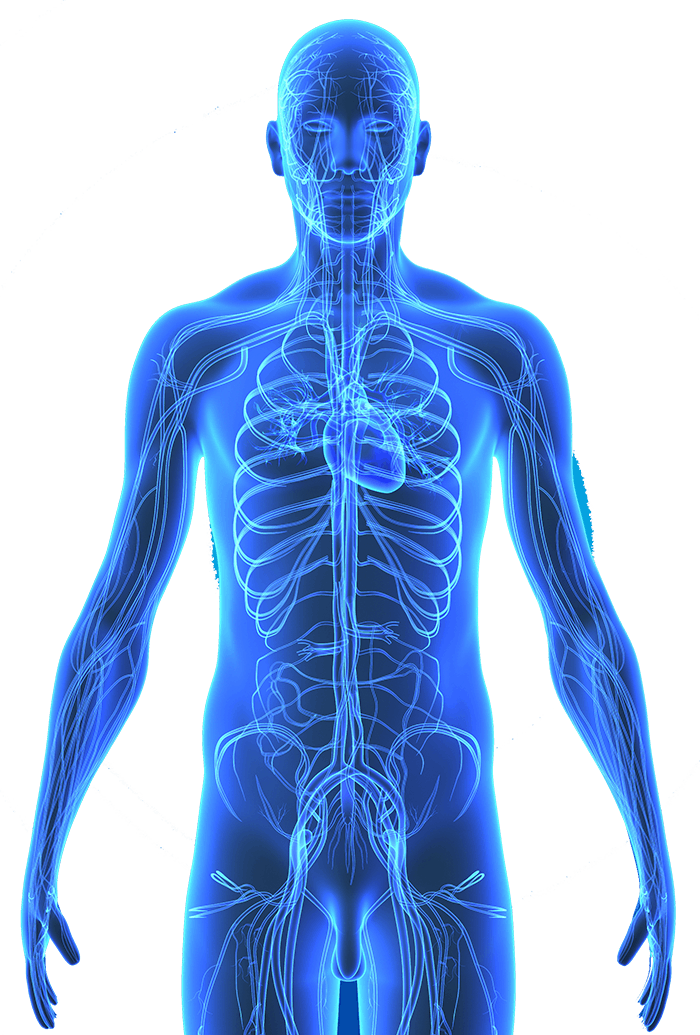

Free Body 1205846 Png With Transparent Background

www.vecteezy.com

www.vecteezy.com

Download Hd Body Centrum Inside Human Body Png Transparent Png Image Nicepng Com

www.nicepng.com

www.nicepng.com

Human Body System Png Image Background Png Arts

www.pngarts.com

www.pngarts.com

Body Download Png Png All

www.pngall.com

www.pngall.com

Download Hd Whole Body Full Body Icon Transparent Png Image Nicepng Com

www.nicepng.com

www.nicepng.com

Vector Human Body Png Photo Png Arts

www.pngarts.com

www.pngarts.com

File Upper Body Front Png Wikimedia Commons

commons.wikimedia.org

commons.wikimedia.org

Body Png Pic Png All

www.pngall.com

www.pngall.com